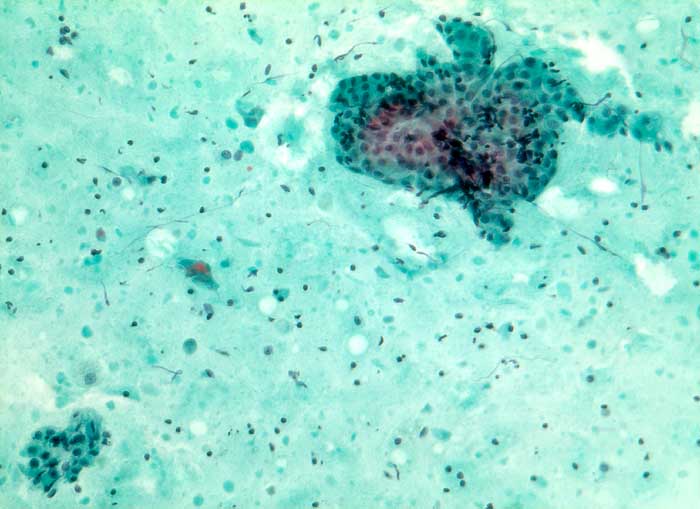

Warthin Tumor

Feinnadelpunktion Parotis: Fein bis grobscholliger Detritus mit einzelnen schattenhaften Zellen und locker verstreuten Lymphozyten. Dazwischen hin und wieder Aggregate onkozytärer Zellen durchmischt mit vereinzelten Lymphozyten.

Unklare Schwellung Parotisunterpol

Zytologie

160